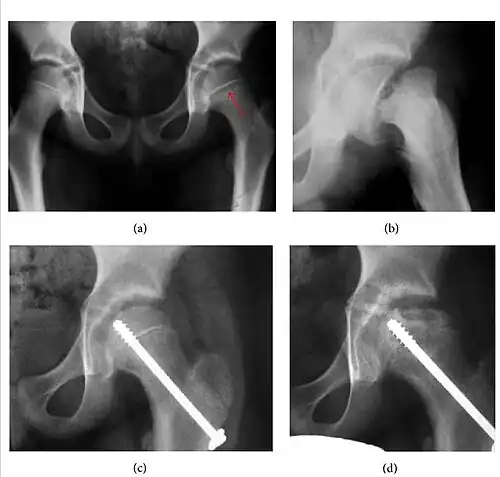

Plain radiography allows us to categorize the hip as normal or dysplastic or with impingement signs (pincer, cam, or a combination of both). Besides these, pathologic processes like osteoarthritis, inflammatory diseases, infection, or tumors can also be identified (Figure 1).[1]

Figure 1.

-

Radiography in normal hip -

X-ray in pincer impingement type of hip dysplasia -

X-ray of cam -

Hip in osteoarthritis -

Septic arthritis

Slipped capital femoral epiphyses (SCFE) usually affect 11- to 14-year-old adolescents (Figure 4). Radiographs may show widening and irregularity of the physis and posterior inferior displacement of the capital femoral epiphysis. On the AP view Klein’s line, tangent to the lateral aspect of the femoral neck, does not intersect the femoral head indicating that it is displaced. SCFE may compromise the blood supply to the femoral head and cause avascular necrosis, mainly when there is instability between the fragments.[1]

Figure 4: (a) X-ray of a 10-year-old child with left hip pain. It was considered normal at emergency despite the widening of the left physis (arrow). Two weeks later epiphysiolysis was evident (b). Despite appropriate surgical reduction (c) osteonecrosis developed and femoral head collapsed 1 month later (d).[1]